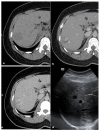

Bilharzia is a parasitic infection particularly affecting the digestive tract and urinary tract. Lung involvement is rarely reported. We report a case of pulmonary bilharzioma of nodular type surrounded by ground glass opacities diagnosed on CT-scan and associated with a hepatic nodule, in a 41-year-old woman. The disappearance of the pulmonary nodule under antischistosomal treatment made it possible to make the diagnosis a posteriori without going through an invasive process.